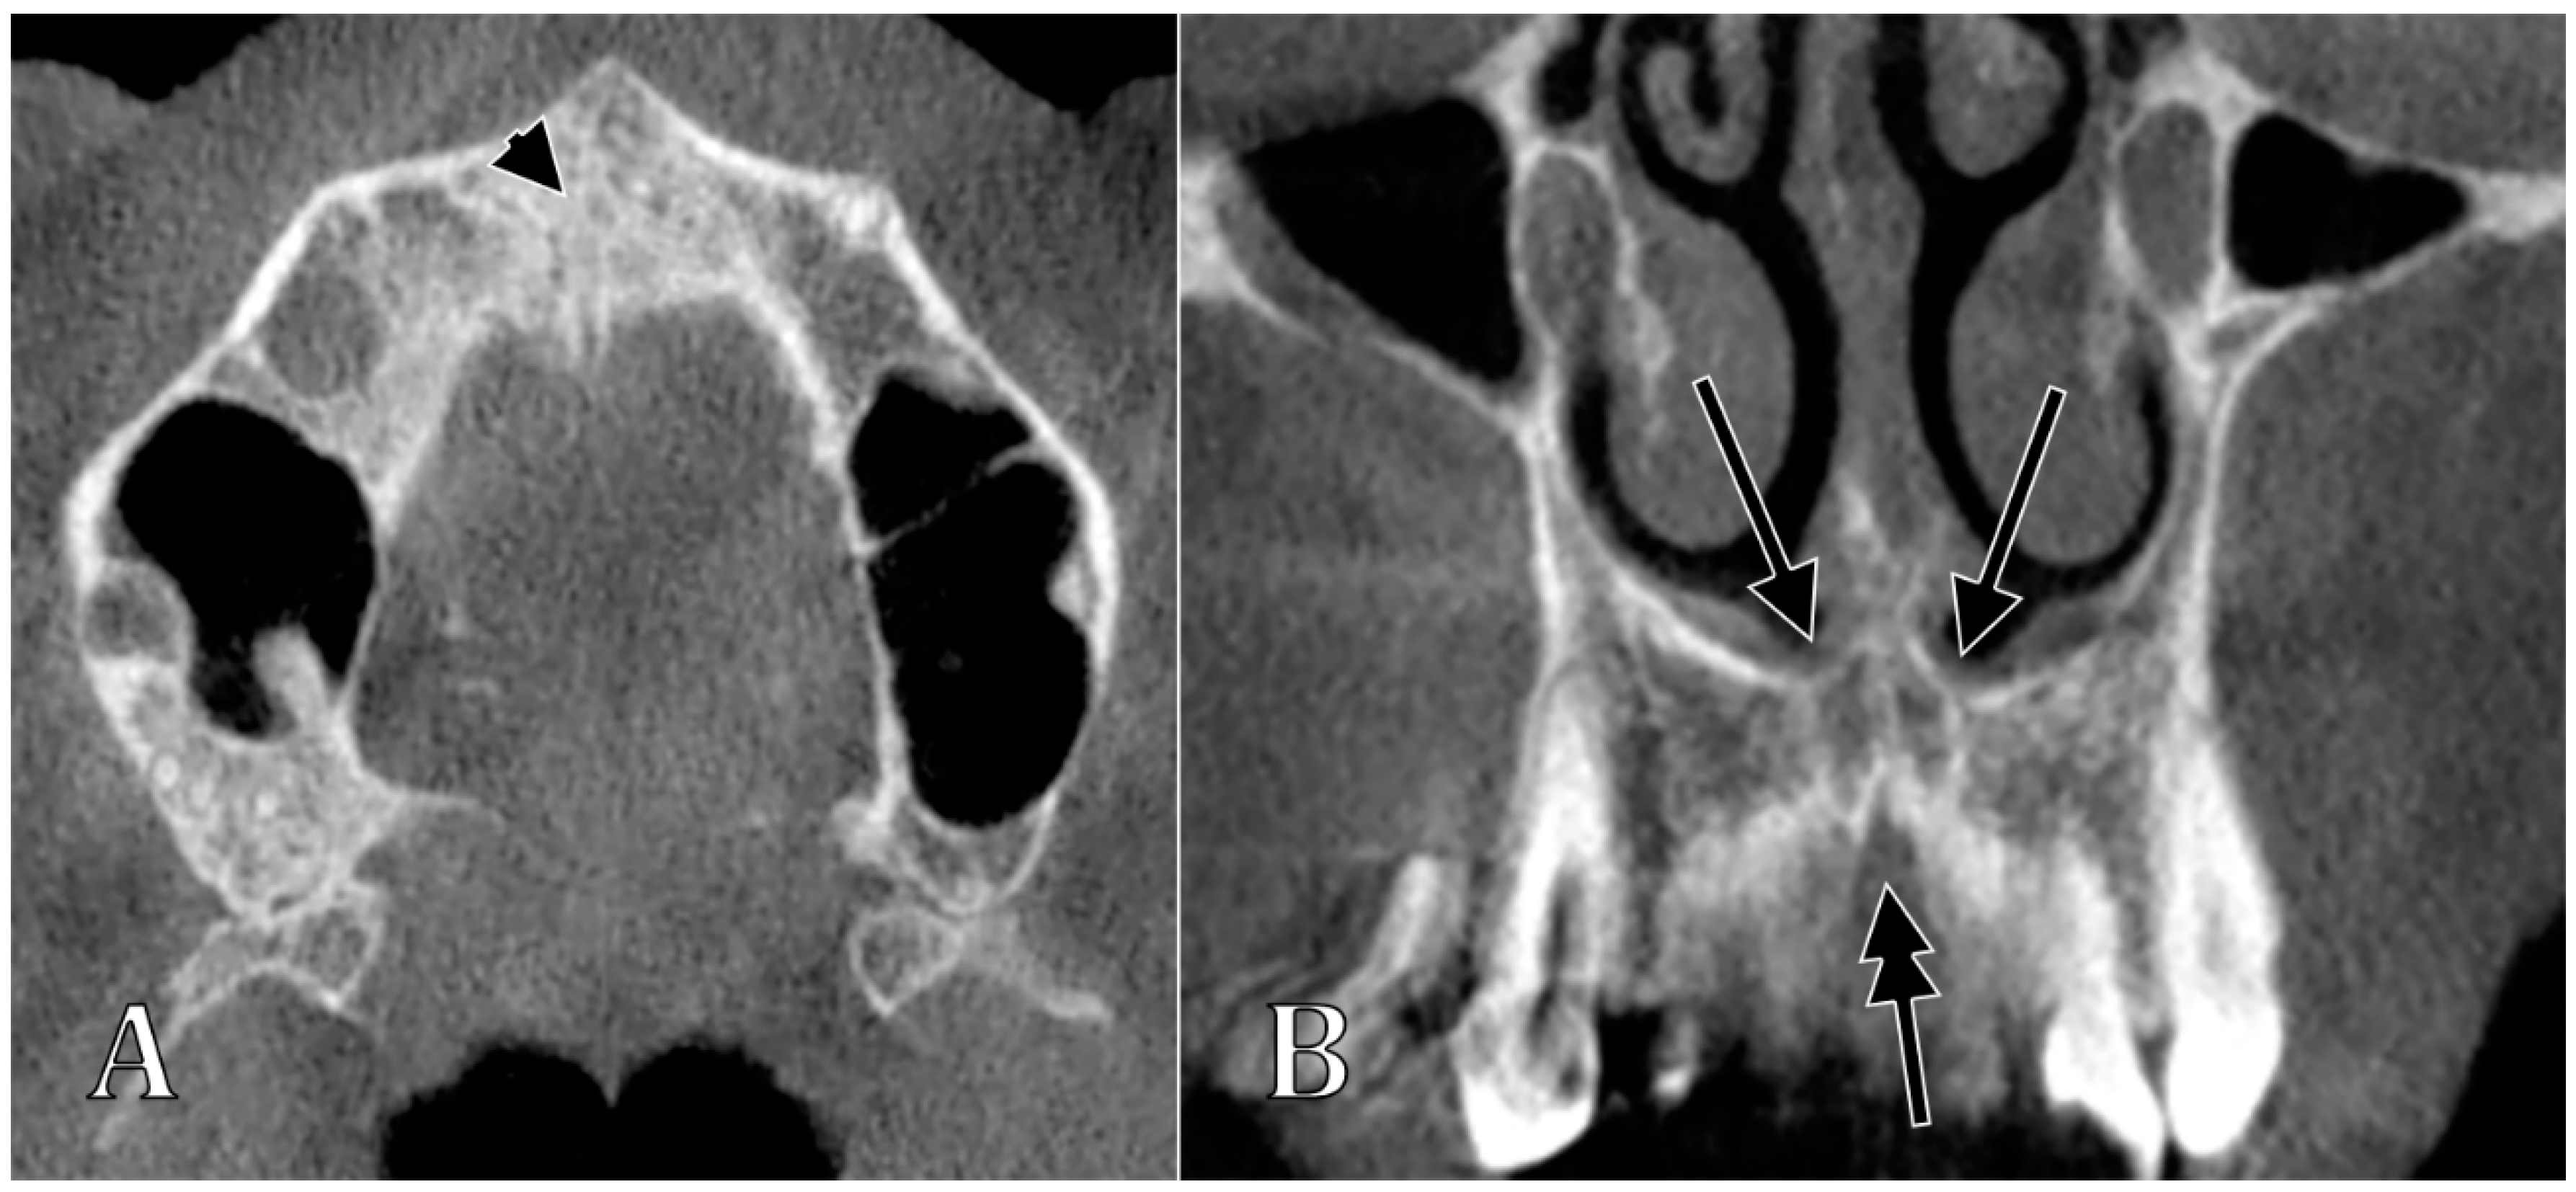

| Type of the NPC/IC | Characteristics of Types | Subtypes | Characteristics of Subtypes |

|---|---|---|---|

| I | NPC/IC present, 2 nasopalatine foramina | Ia | “Y”-shaped NPC/IC, with no secondary canaliculi |

| Ib | “Y”-shaped NPC/IC, with secondary canaliculi separated by a sagittal septum | ||

| Ic | “Y”-shaped NPC/IC, with unilateral secondary canaliculi separated by a coronal septum | ||

| Id | “Y”-shaped NPC/IC, with bilateral secondary canaliculi separated by a coronal septum | ||

| Ie | “Y”-shaped NPC/IC, with an added superiorly blind-ended median canal | ||

| If | parallel proper NPCs/ICs separated by septum | ||

| Ig | parallel proper NPCs/ICs unseparated by septum (NPC/IC unique, two nasopalatine foramina) | ||

| II | NPC/IC absent, 2 nasopalatine foramina | ||

| III | NPC/IC unique, 1 nasopalatine foramen | IIIa | unique median nasopalatine foramen, inferior to the nasomaxillary crest |

| IIIb | unique median nasopalatine foramen, on one side of the nasomaxillary crest | ||

| IV | NPC/IC present, 3 nasopalatine foramina, 1 median and 2 lateral | ||

| V | NPC/IC proper absent, absent nasopalatine foramina |